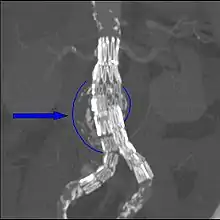

يشخص تمدد الشريان الأبهري البطني عادة بواسطة فحص بدني، أو بمسح الموجات فوق الصوتية، أو بالتصوير المقطعي. قد تظهر صور أشعة البطن الخطوط العريضة لتمدد الأوعية الدموية عندما تكون جدرانه متكلسة. وهذا هو الحال في أقل من نصف حالات تمدد الأوعية الدموية. يستخدم التصوير بالموجات فوق الصوتية للكشف عن تمدد الأوعية الدموية وتحديد حجم أي من الموجود. بالإضافة إلى ذلك، يمكن الكشف عن السائل البريتوني وهى من الوسائل الغير تداخلية وذات حساسية عالية، ولكن وجود الغازات في الأمعاء أو وجود السمنة قد يحد من فائدتها. الاشعة المقطعية ذو حساسية لاكتشاف تمدد الأوعية الدموية ما يقرب من 100 ٪ ومفيد أيضا في التخطيط السابق للجراحة، تفاصيل التشريح وتركيب جسم المريض وإمكانية إصلاح الأوعية الدموية من الداخل. في حالة تمزق التمددالمشتبه به، فإن يمكنه أيضا الكشف عن السوائل خلف البريتون. بدائل قليلا ما تستخدم كأساليب التصوير لتمدد الأوعية الدموية وتشمل التصوير بالرنين المغناطيسي وتصوير الأوعية.

تعزيز الاشعة المقطعية يدل على وجود تمدد الشريان الأورطي البطني ب4.8 بنسبة 3.8 سم